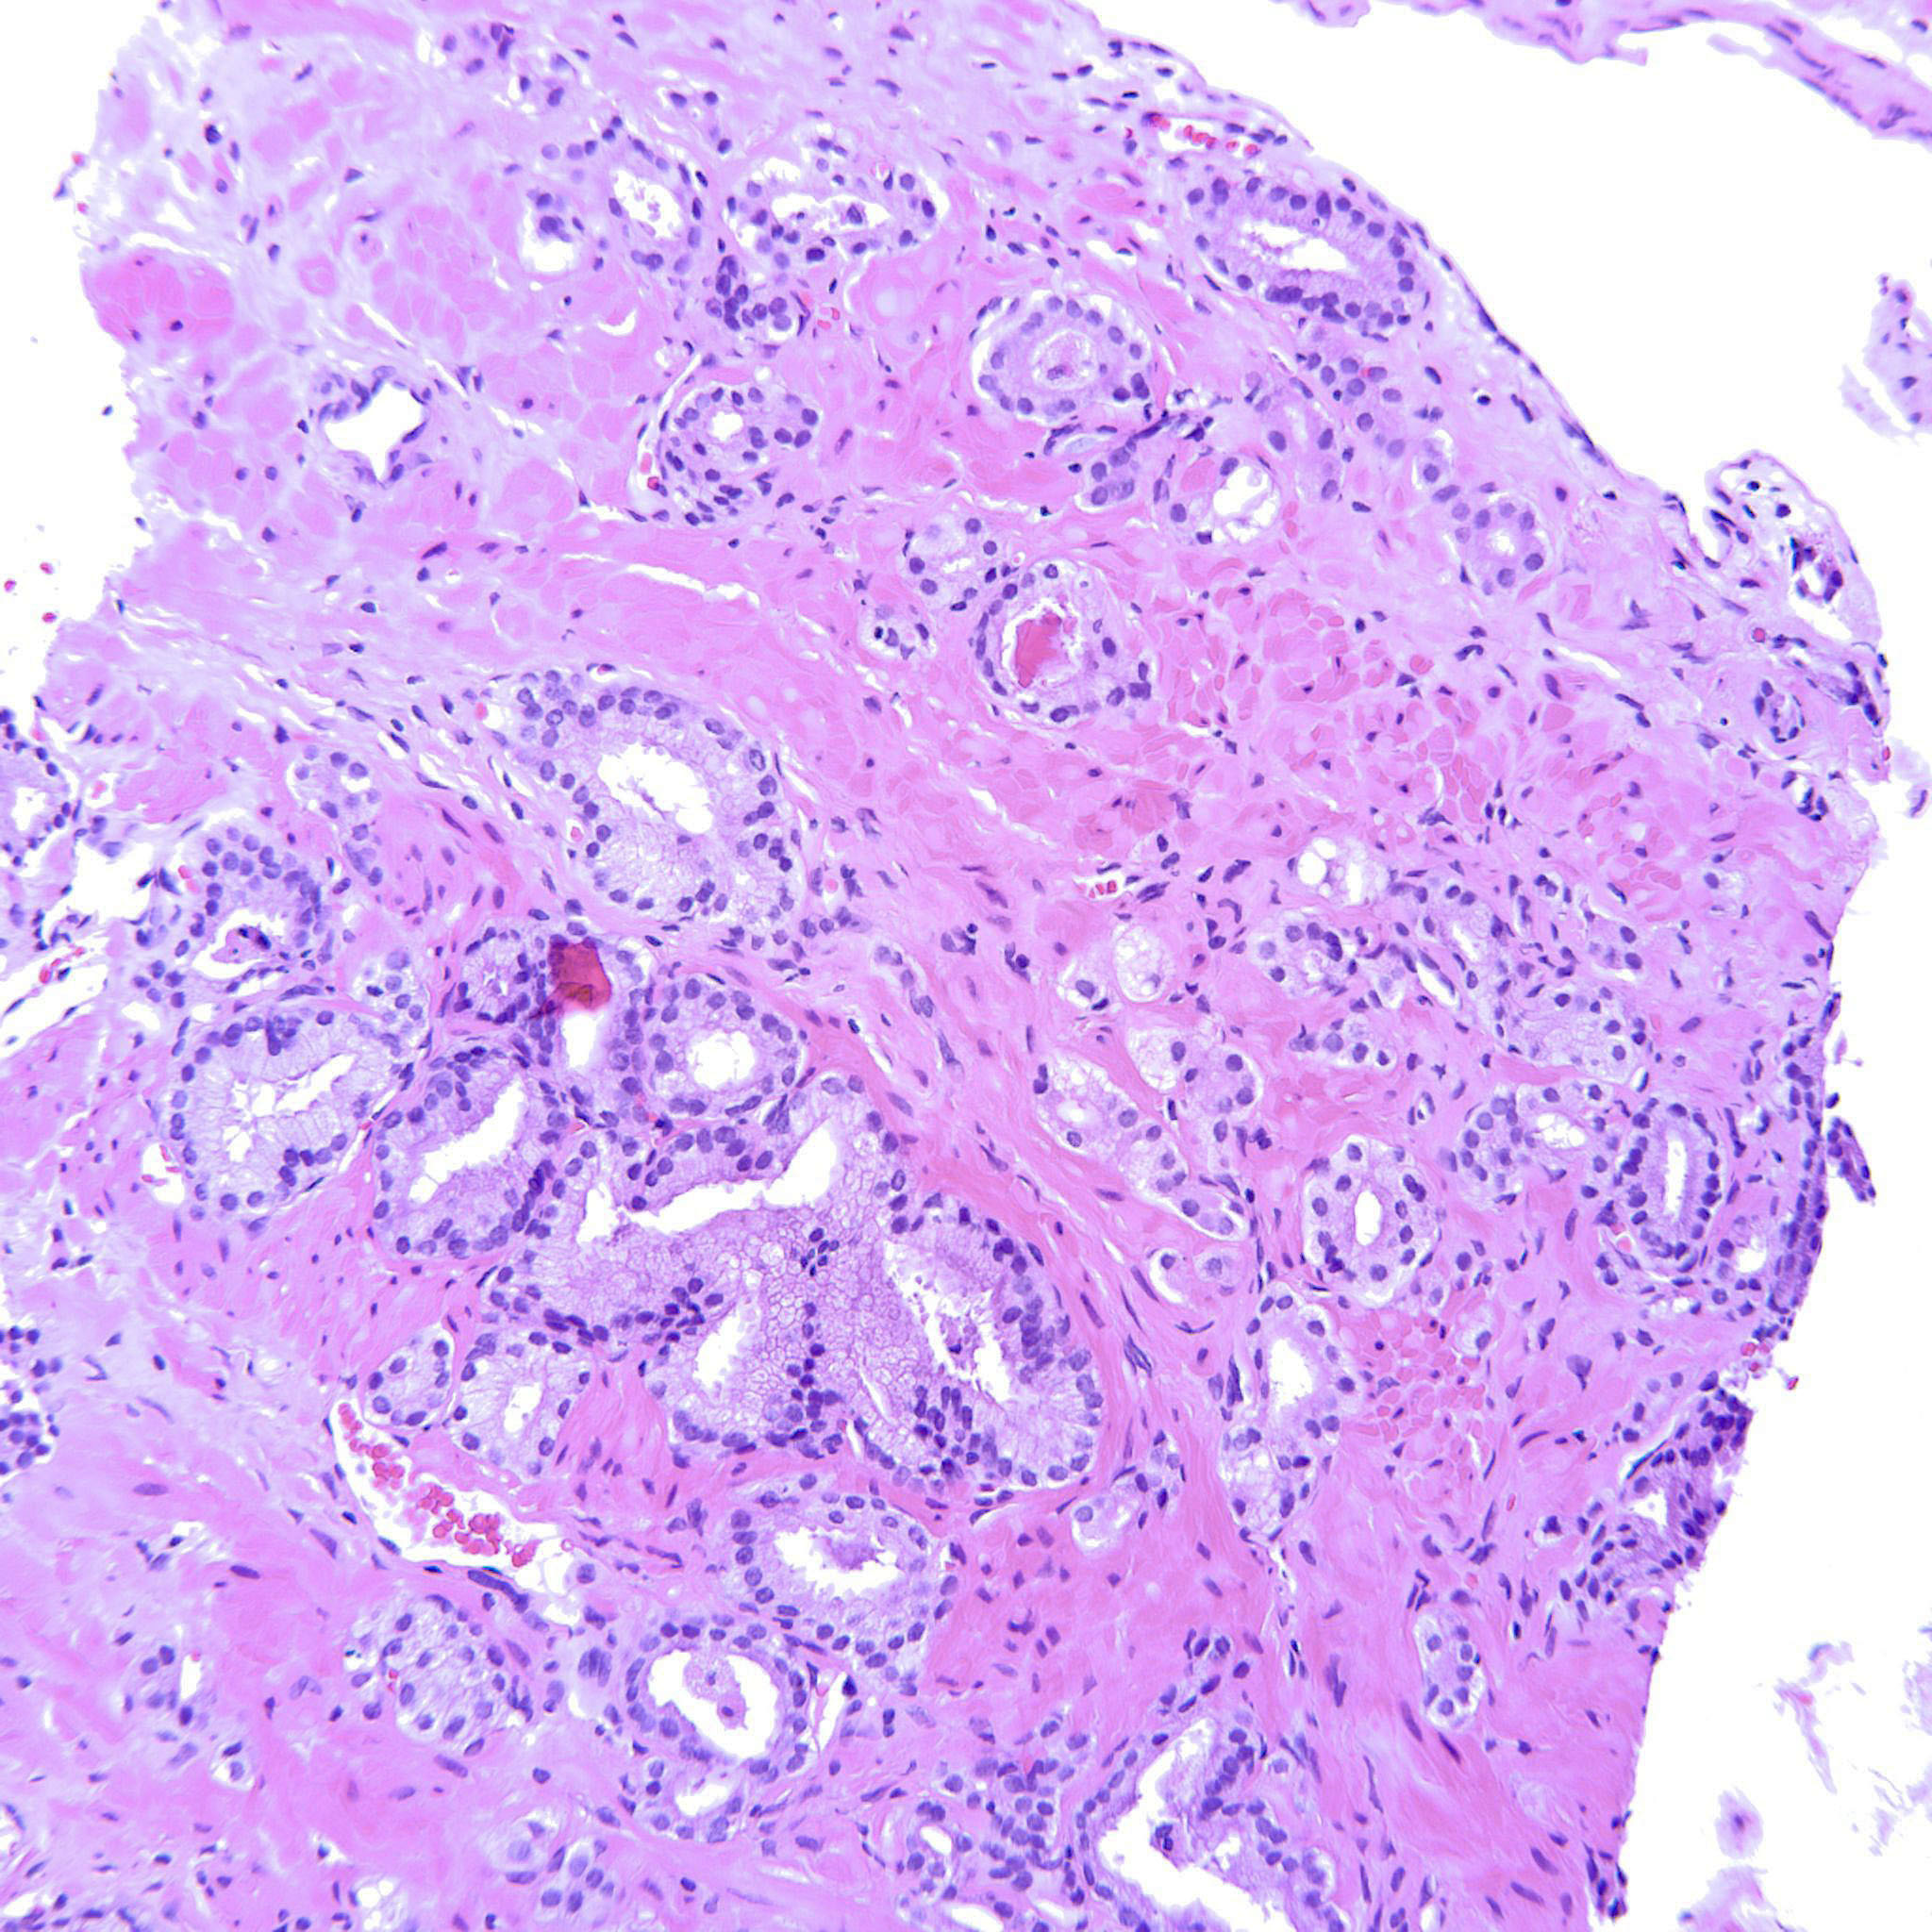

Consensus grade: GS 3+4=7 (ISUP 2)

The issue here is threshold for the number of poorly formed acini required to call pattern 4. I would need to see at least 3 levels to be most confident in assigning a grade |

5-10% pattern 4 |

Poorly formed glands. "Single cells" interpreted as tangential sectioning. |

Most of the tumor is GP3 but there are also some poorly formed glands.